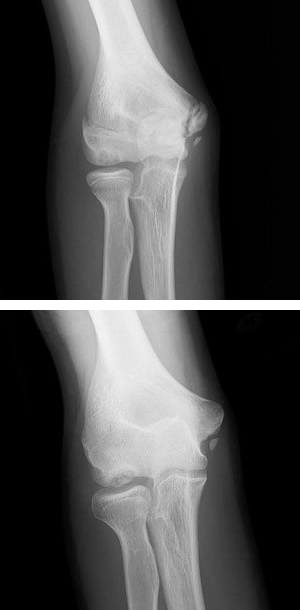

離断性骨軟骨炎

離断性骨軟骨炎 Wikipedia